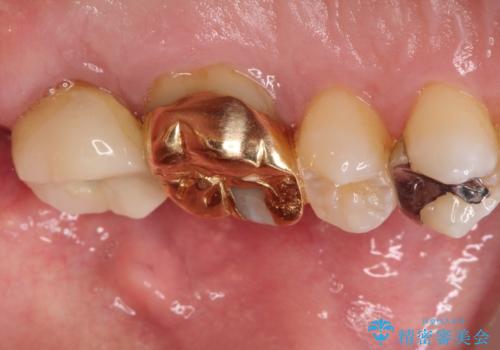

目立つ金歯を自然な色のオールセラミックへ

- 矯正の治療後に目立つ金歯を白くしたいとのことで治療することとなりました。

左上の奥歯に大きな金歯と、その後ろの歯が矯正治療用の仮歯が装着されていました。

これらの歯にオールセラミッククラウンを装着することとなりました。